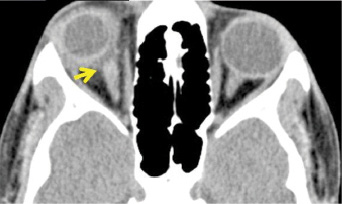

A 16-year-old boy presented with sudden loss of vision in his right eye after sustaining a blunt injury from a cricket ball. External examination of the eye revealed lid edema and subconjunctival hemorrhage. The patient's VA at presentation was no light perception. Fundus examination revealed an excavation in the optic nerve head region with absent optic disc (image below).

The rim of the excavation showed cicatricial tissue, blood, and multiple peripapillary hemorrhages. The entirety of the retina was edematous, associated with cattle-tracking of vessels and arteriolar attenuation suggestive of central retinal artery occlusion (CRAO) (image below, left).